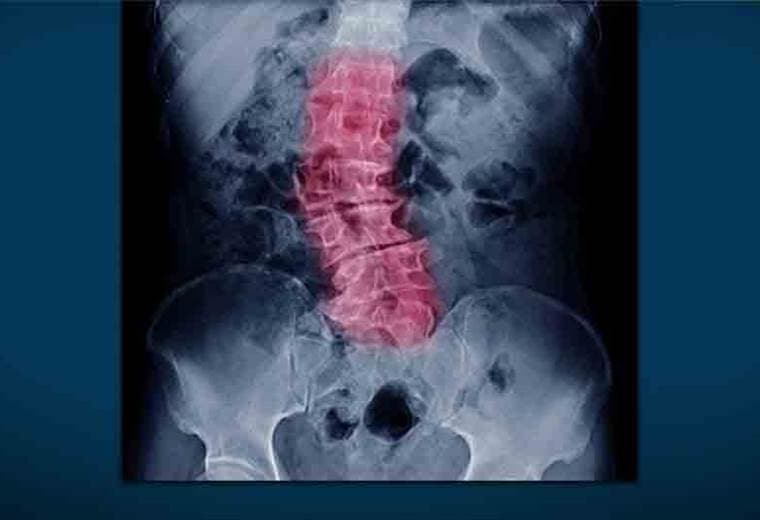

Es normal que nuestra columna no sea del todo recta, pero hay casos extremos en los que se deforma al punto de formar una "c" o una "s".

Esto se conoce como escoliosis y después de los 40 años es un padecimiento más común de lo que pensamos; a tal punto que uno de cada dos adultos mayores lo presenta.